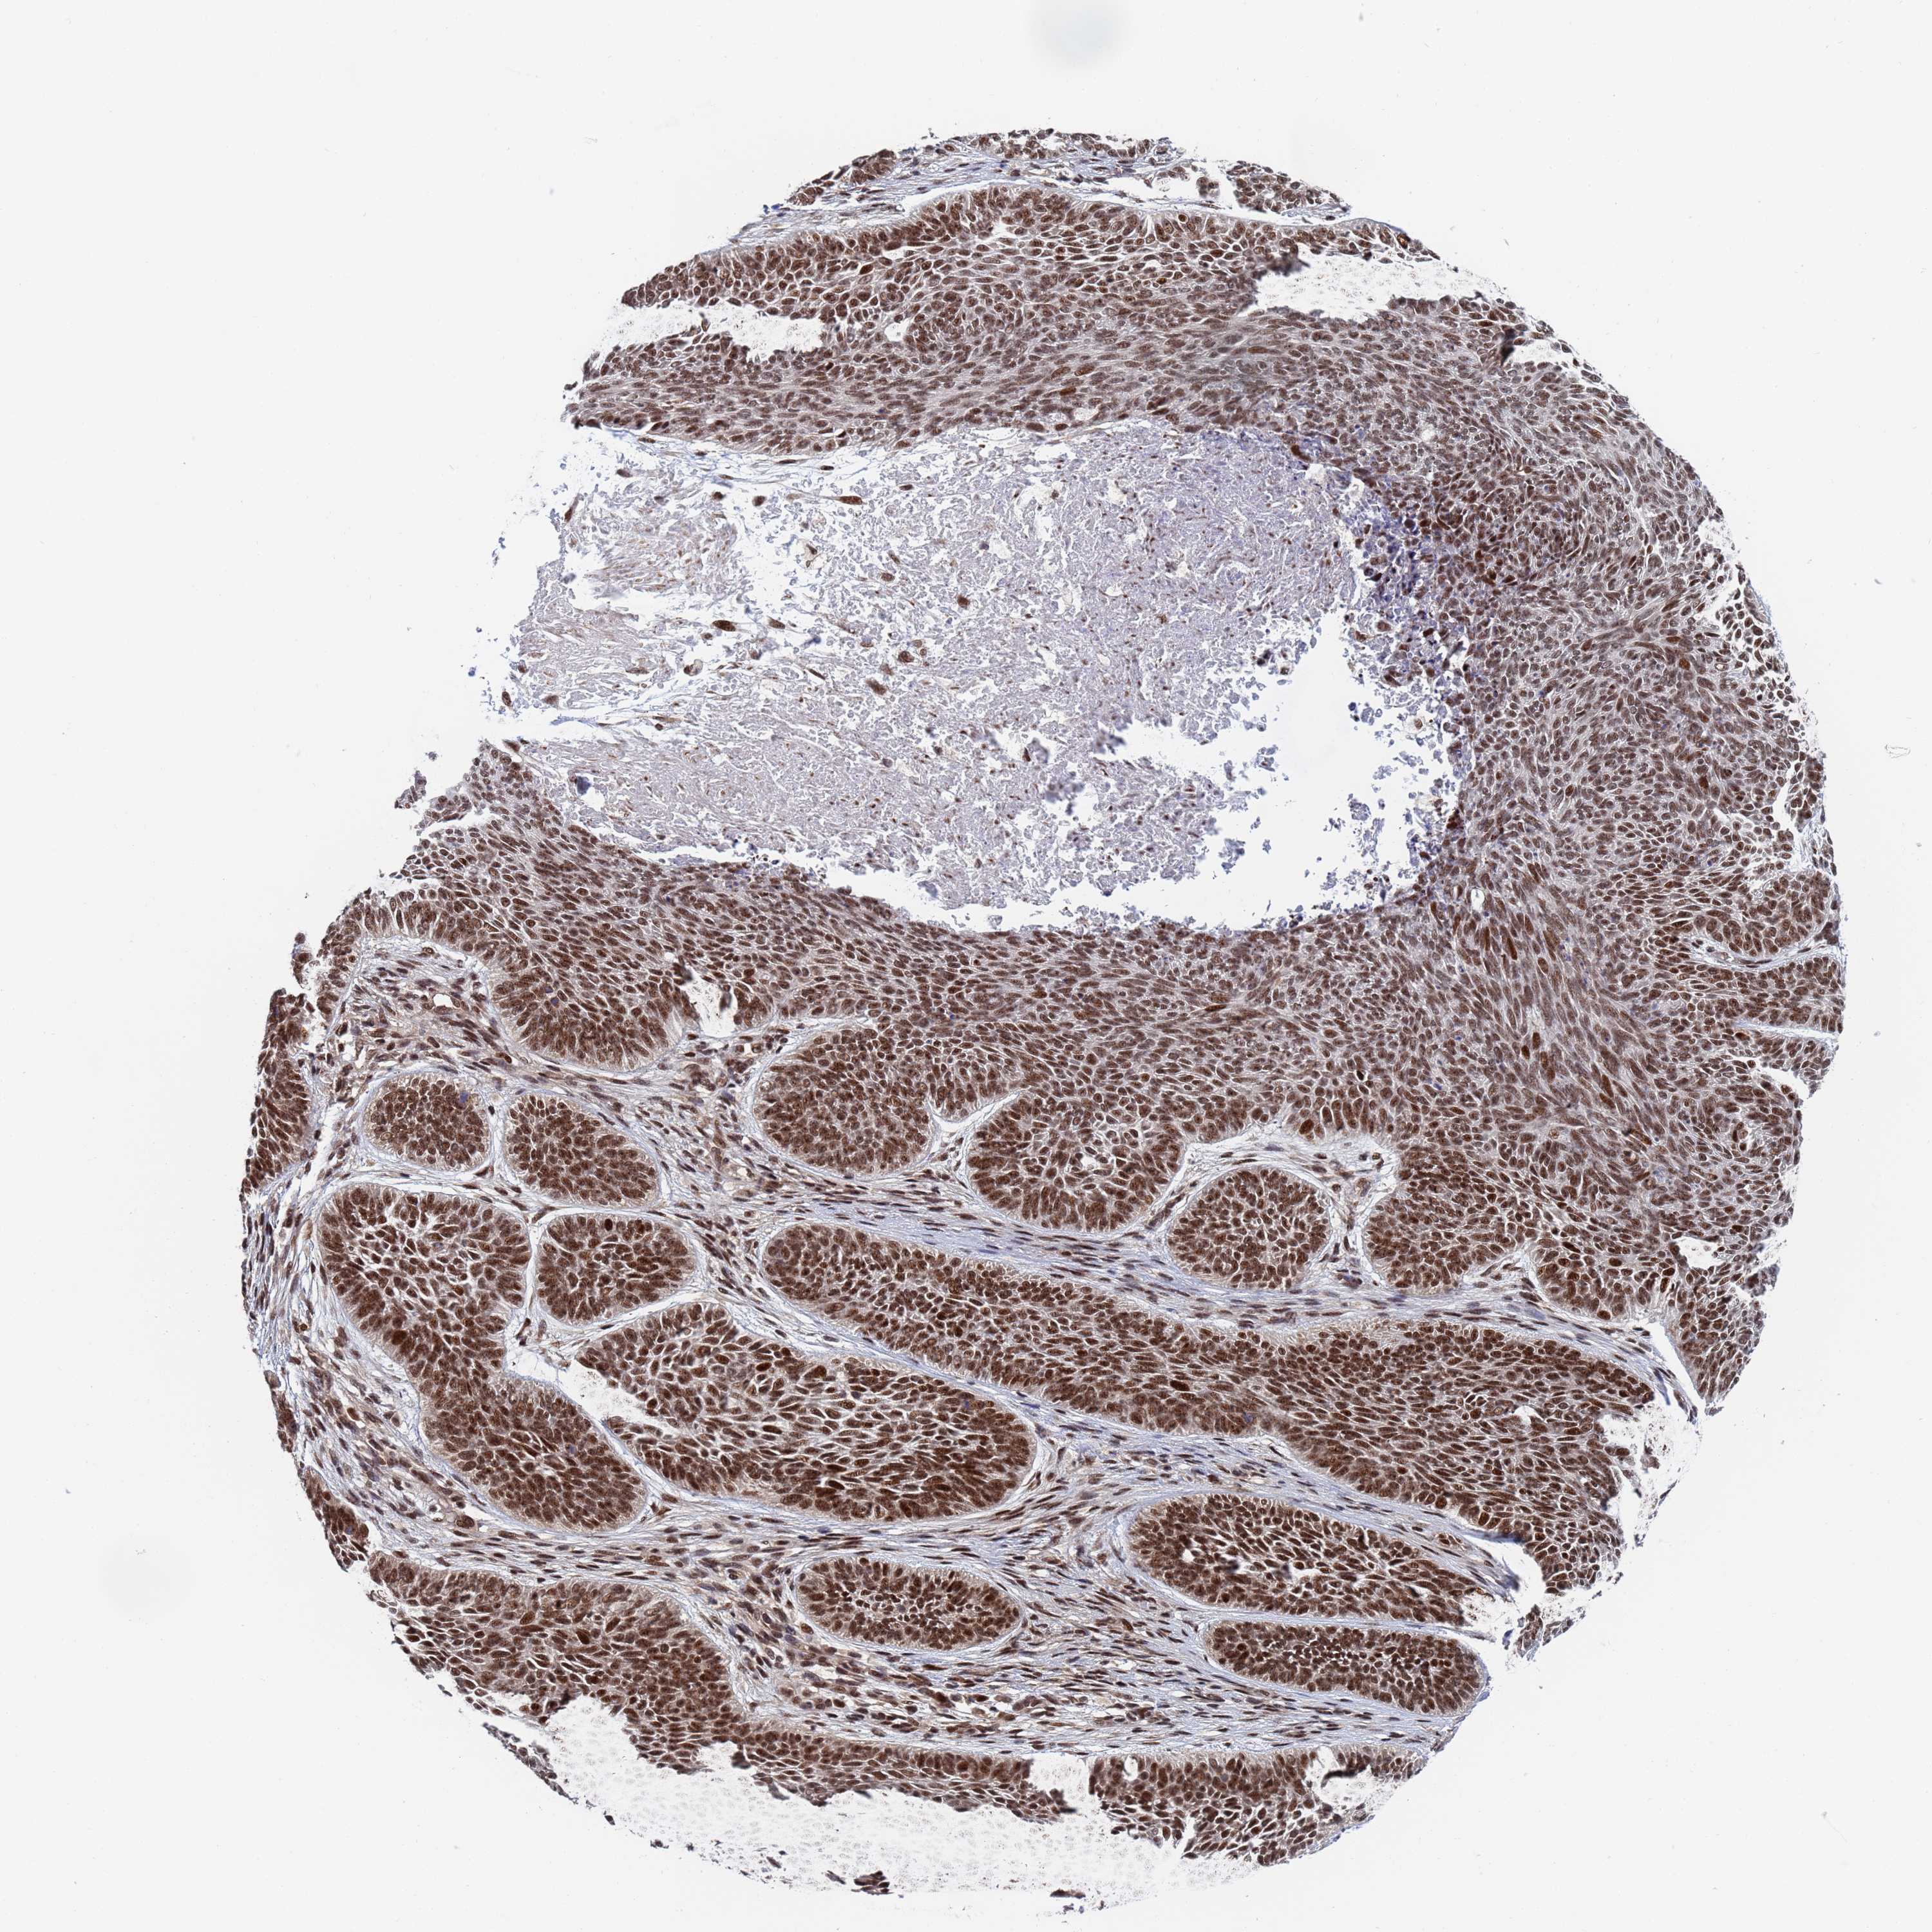

SKIN CANCER - Protein expressioni

A mouse-over function shows sample information and annotation data. Click on an image to view it in a full screen mode. Samples can be filtered based on level of antibody staining by selecting one or several of the following categories: high, medium, low and not detected. The assay and annotation is described here.

Each image is clickable and will lead to virtual microscopy that enables deeper exploration of all samples and also displays staining intensity scores, fraction scores and subcellular localization as well as patient and tissue information for each sample.

Antibody HPA035693

Staining

High

Intensity

Strong

Quantity

>75%

Location

Nuclear

Squamous cell carcinoma, metastatic, NOS

Squamous cell carcinoma, NOS